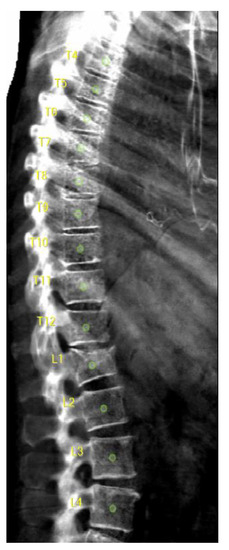

2.3. DXA-VFA Image Annotation

3.1. Vertebral Level Assignment

3.2. Point-Wise Landmark Annotation Accuracy